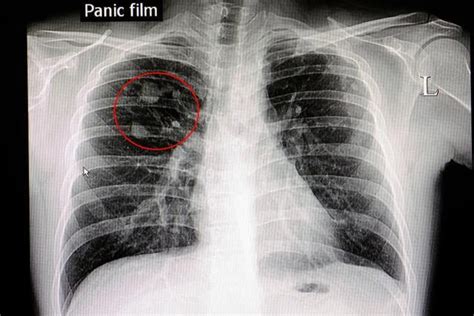

肺炎 作者:佚名 医学专科来源:本站原创 点击数:33 更新时间:2005-10-5 疾病概述 病程超过3个月者为慢性肺炎。近年来小儿急性肺炎病死率正在降低,但重症肺炎患儿有时未彻底恢复,复发和演变成慢性肺炎者颇不少见。因此,及时地防治慢性肺炎非常重要。 病因病理 病因学: 促成慢性肺炎的因素有以下几种:①营养不良、佝偻病、先天性心脏病或肺结核患儿发生肺炎时,易致病程迁延。②病毒感染引起间质性肺炎,易演变为慢性肺炎。首都儿科研究所曾对103例腺病毒肺炎在病后1~5年随访,发现30.1%在X线检查时呈现轻重不等的慢性肺炎和肺不张,个别患儿还有支气管扩张。对13例麻疹并发腺病毒肺炎在病后2~3年随访,其中6例已成为慢性肺炎。③反复发生的上呼吸道感染或支气管炎以及慢性鼻窦炎均为慢性肺炎的诱因。④深入支气管的异物,特别是缺乏刺激性而不产生初期急性发热的异物(如枣核等),可被忽视而长期存留在肺部,形成慢性肺炎。⑤免疫缺陷小儿,包括体液及细胞免疫缺陷,补体缺乏及白细胞吞噬功能缺陷皆可致肺炎反复发作,最后变成慢性。⑥原发性或继发性呼吸道纤毛形态及功能异常可致肺慢性炎症。 病理改变: 炎症病变可侵及各级支气管、肺泡、间质组织和血管。特别在间质组织的炎症,每次发作时都有所进展,使支气管壁弹力纤维破坏,终因纤维化而致管腔狭窄。同时,由于分泌物堵塞管腔而发生肺不张,终致支气管扩张。由于支气管壁及肺泡间壁的破坏,空气经过淋巴管散布,进入组织间隙,可形成间质性肺气肿。局部血管及淋巴管也发生增生性炎症,管壁增厚,管腔狭窄。 临床表现 慢性肺炎的特点是周期性的复发和恶化,呈波浪型经过。由于病变的时期、年龄和个体的不同,症状多种多样。在静止期体温正常,无明显体征,几乎没有咳嗽,但在跑步和上楼时容易气喘。在恶化期常伴有肺功能不全,出现发绀和呼吸困难,并由于肺活量和呼吸储备减少及屏气时间缩短等,引起过度通气的外呼吸功能障碍。恶化后好转很缓慢,经常咳痰,甚至出现面部浮肿、发绀、胸廓变形和杵状指、趾。由于肺气肿、肺功能不全而引起肺循环阻力增高,肺动脉压力增高,右心负担加重,可在半年至两年内发生肺原性心脏病。还可能有肝功能障碍。白细胞增加,血沉中度增快。 X线胸片显示在两肺中下野及肺门区肺纹理可呈蜂窝状,出现小泡性肺气肿,同时还可伴有实质性炎症病灶。两侧肺门阴影可见对称性增大。随病变的发展还可发生支气管扩张、右心室肥大及肺动脉段突出等肺原性心脏病的X线征象。有肺原性心脏病时,心电图表现顺钟向转位,P波高而尖,QRS综合波多数出现右心室肥厚图型等改变。 诊断鉴别 在本病的诊断中病史极为重要,往往曾反复发生鼻窦炎、支气管炎或肺炎,或曾患麻疹、百日咳、流行性感冒或腺病毒肺炎。确定诊断需要结合病史、症状和丝检查。 鉴别诊断: 要特别注意与结核病鉴别。反复发生上、下呼吸道感染或传染病后肺部感染迁延不愈的历史,以及排出脓样痰等,多见于慢性肺炎。结核菌素试验和X线检查,肺门及气管旁淋巴结肿大,可协助诊断。 治疗预防 对本症的治疗需长期坚持综合措施。治疗要点如下: (1)加强营养:供给富有营养及维生素的饮食。积极治疗营养不良及佝偻病。 (2)锻炼体格:经常做户外活动或户外睡眠。进行体操、冷水擦浴或冷水浴等锻炼,增强机体的耐寒性。室内宜通风换气,保持空气新鲜。积极预防呼吸道感染。 (3)中医疗法:主要是补益全身和恢复肺功能,参阅支气管肺炎中医疗法节和肺炎恢复期治疗。 (4)清除病灶:如有鼻窦炎及支气管扩张等并存时,应采取适当治疗或外科手术治疗。 (5)其它疗法:雾化吸入适当的抗生素,反复感染时应用抗生素控制感染。肾上腺皮质激素可起到抑制增生和促进病灶呼吸的作用。天津儿童医院曾用强的松治疗5例,用药2~12月,效果良好。此外,又可用电磁疗法,超短波透热,按摩及芥末敷等物理疗法。 预防: 肺炎病理的恢复比临床恢复晚。因此,在重症肺炎的恢复期应进行理疗和体操,积极治疗并发的佝偻病和营养不良,并于出院后随访和继续治疗,直至彻底痊愈为止。此外,婴幼儿时期应设法预防麻疹、百口咳、流感和腺病毒感染。对漫性鼻窦炎及反复发生的支气管炎,也应积极防治。有免疫缺陷的患儿可采用免疫促进疗法,根据具体情况分别选 用人血丙种球蛋白、转移因子、胸腺素或中药治疗,必要时可采用骨髓移植以重建免疫功能,防治反复感染及慢性肺炎的发生。

建议:你好,肺炎的症状很多,而且年龄不一样,表现不一样。 根据宝宝的情况,一般肺炎主要表现是咳嗽,有小小儿,咳嗽不剧烈但是有喘息,喉间有痰。主要是肺部听诊可以听到罗音甚至是喘鸣音。胸片显示有阴影。建议你多给宝宝拍背。可以考虑给宝宝雾化吸入。